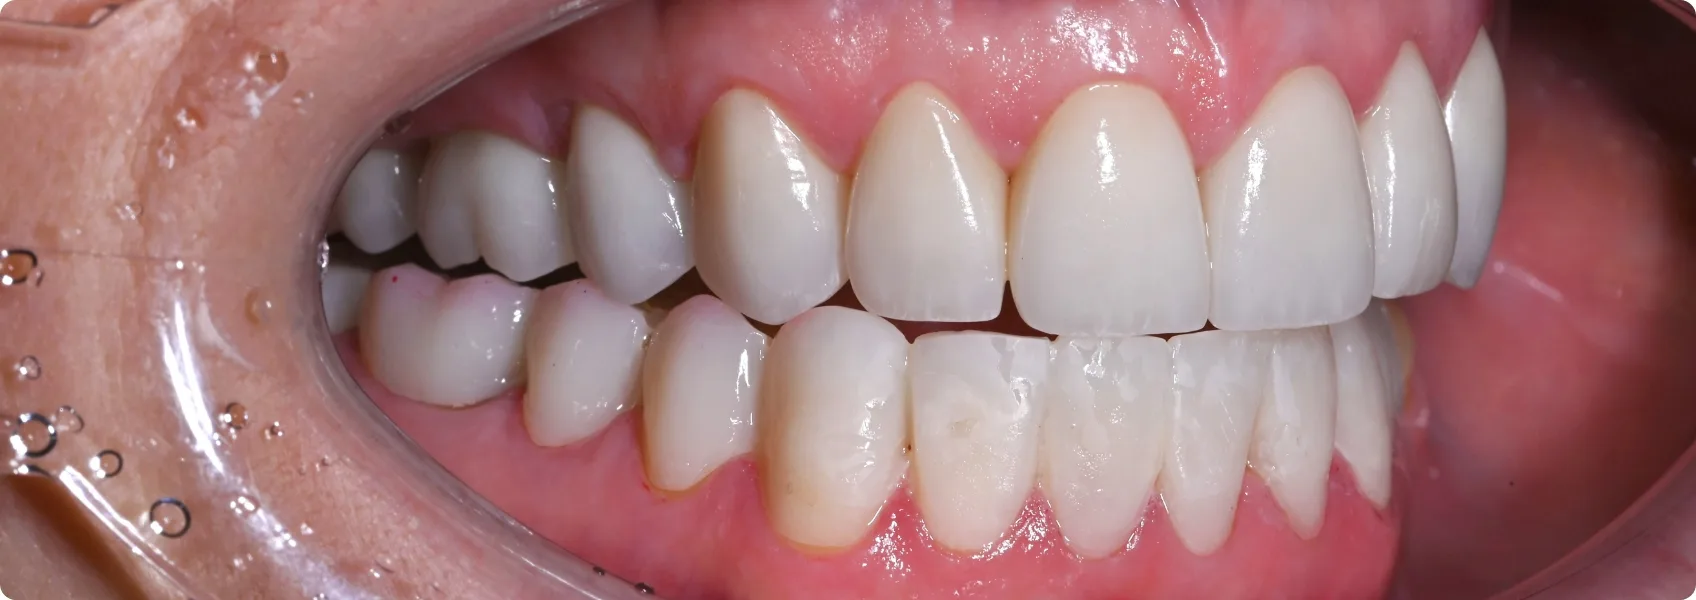

Na górze korony pełnoceramiczne, na dole jeszcze “tymczasówka”.

Finalnie doktor Ewa w łuku górnym założyła przygotowane korony pełnoceramiczne.

W łuku dolnym na zdjęciach widoczna jest jeszcze rekonstrukcja w formie tymczasowej – długoczasowej. Taka “tymczasówka” nie jest na stałe. Nie wygląda zbyt naturalnie, a po kilku miesiącach zaczyna przebarwiać się wskutek wnikania w materiał barwników z jedzenia. Można ją jednak nosić w oczekiwaniu na dalsze etapy leczenia.

Przywróciliśmy funkcję — prawidłowe kontakty pomiędzy zębami górnymi i dolnymi.

Genialnie wręcz odbudowane prowadzenia boczne i przednie sprawiły, że zęby przestały wreszcie nieprawidłowo trzeć o siebie. Doktor Ewa przywróciła nie tylko estetykę, ale przede wszystkim prawidłową funkcję zębów. Pacjentka przestała cierpieć na bolesną nadwrażliwość.